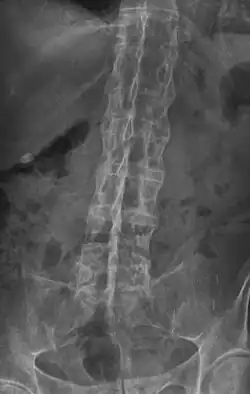

Hauptvorgang bei Spondylitis ankylosans ist die Entzündung der Sehnenansätze, besonders an Becken und Wirbelsäule. Begleitet wird diese durch Ödeme und Schäden am Knochenmark, das dann verknöchert. Die Entzündung des Kreuzbein-Darmbeingelenks (Sakroiliitis) ist eine der ersten Erscheinungen. Betroffen sind dabei sowohl Sehnenansatz als auch Gelenkkapsel. Unterhalb des Gelenkknorpels bildet sich Granulationsgewebe, mit Infiltration durch Lymphozyten und Makrophagen. Die beschädigten Ränder der Gelenke werden zuerst durch Faserknorpel ersetzt, verknöchern dann aber, wodurch das Gelenk versteift wird. In der Wirbelsäule kommt es durch diesen Prozess zur Bildung von Knochenspangen (Syndesmophyten), die benachbarte Wirbel überbrücken. Dies führt zur Bildung der sogenannten Bambuswirbelsäule. Weitere Schäden an der Wirbelsäule sind Osteoporose, Abnutzung der Wirbelkörper an den Rändern und Entzündung mit anschließender Zerstörung der Übergänge zwischen Bandscheibe und Knochen.

Erosion, reaktive Verkalkungen, und Verknöcherung der Articulatio sacro-iliaca waren seit den 1930er Jahren die ersten pathognomonische Symptome der Spondylitis ankylosans. In späteren Stadien kann es zu Knochenspangen zwischen benachbarten Wirbeln und Verknöcherungen des Wirbelkörperbandapparates kommen. Die Verknöcherung der Wirbelsäule ist auf Röntgenbildern gut zu erkennen und wird wegen ihrer markanten Form auch als Bambuswirbelsäule bezeichnet.